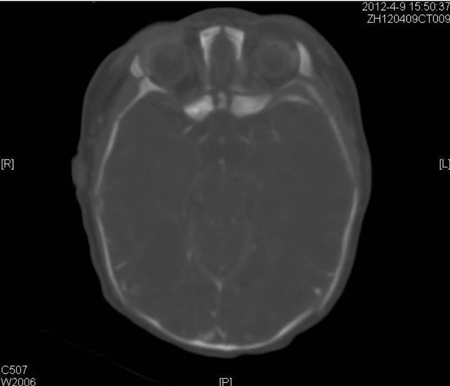

A healthy 40-year-old, gravida 5 and para 5, woman delivered a male infant weighing 2.89 kg by spontaneous vaginal delivery at term. There was neither a family background of congenital malformations nor a history of any medications during the pregnancy. The prenatal course was uncomplicated. On examination, the baby showed absence of the nose, nasal root, nasal pits; microphthalmia, auris dextra microtia, right side anorchia, small penis, high arched palate, hypoplasia of bilateral maxillary sinus and ethmoid sinus (Fig. 1-3). There were longitudinal ridge-like protuberances in the mid-face. Shortly, the infant was transferred to the neonatal intensive care unit for further evaluation and monitoring. The baby had severe shortness of breath which was relieved by an oropharyngeal tube. Karyotyping performed was 46 XY. The dyspnea and tachypnea greatly improved one month later and the baby adapted to oral breathing and feeding simultaneously. Further work-up including echocardiogram, CT brain, and blood chemistry, all were normal.

Figure 2: CT scan showing microphthalmia |